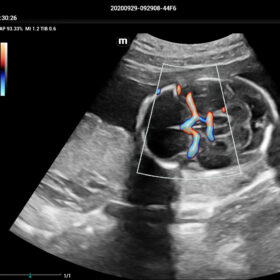

Comprehensive Imaging Solutions Powered by ZST+

The ZST+ platform is a remarkable advancement, marking a significant evolution in ultrasound technology. It revolutionizes the processing of ultrasound metrics, moving away from the traditional beam-forming approach to channel data-based processing. This breakthrough eliminates the longstanding trade-off challenges between spatial resolution, temporal resolution, and tissue uniformity. The result is outstanding image quality, providing limitless imaging solutions with continuous enhancements.

- HR-Flow Improving the hemodynamic presentation

Cardiovascular Solution

- Auto EF– Automatic measurement of ejection fraction by diastole/systole frames

- TTQA-Myocardial sychronization evaluation with quantitive analysis

- RIMT-RF data based real-time IMT measurement